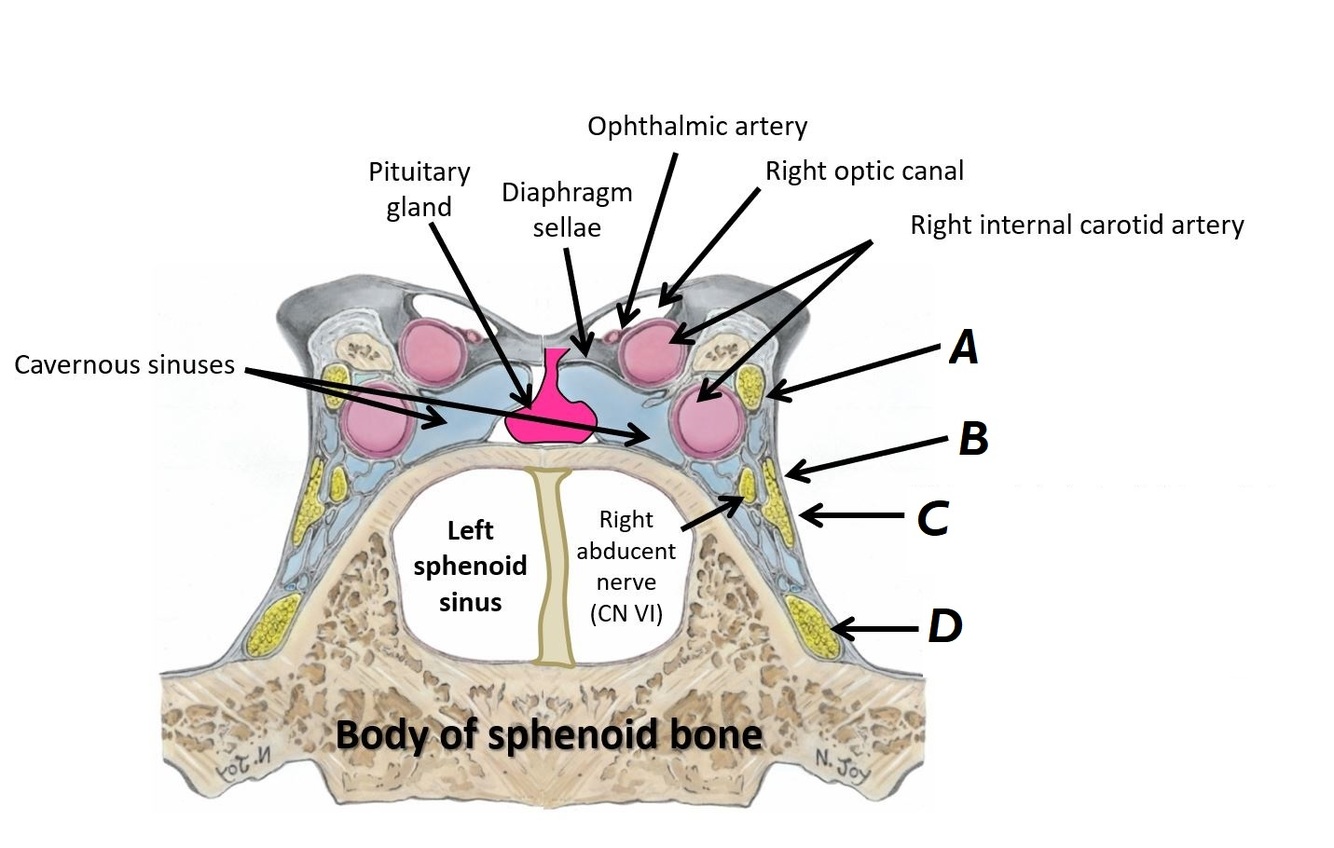

Name nerves A to D

A - Right oculomotor nerve (CN III)

B - Right trochlear nerve (CN IV)

C - Right opthalmic division of trigeminal nerve (CN V1)

D - Right maxillary division of trigeminal nerve (CN V2)